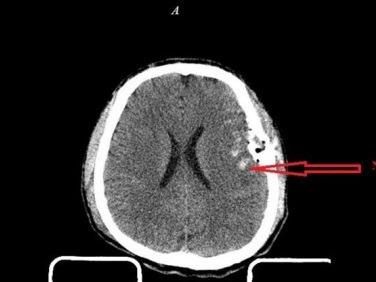

Dập não và dập não kèm xuất huyết

Trên cơ sở tổn thương não tiên phát (giập não hoặc máu tụ) xảy ra ngay sau chấn thương sẽ dẫn tới tổn thương não thứ phát là do hậu quả của rối loạn vận mạch, rối loạn thần kinh thể dịch... dẫn tới phù não và làm cho áp lực nội sọ tăng cao. Hậu quả tăng áp lực nội sọ dẫn tới tụt kẹt não. Tổn thương não tiên phát và thứ phát làm cho tình trạng bệnh ngày một trầm trọng hơn.

Khi tăng tốc và giảm tốc đột ngột làm cho não trong hộp sọ trượt trên các gờ xương đồng thời xoay, xoắn vặn, giằng xé gây tổn thương não nặng nề và phức tạp như giập não lớn, giập thân não, đứt rách các mạch máu...